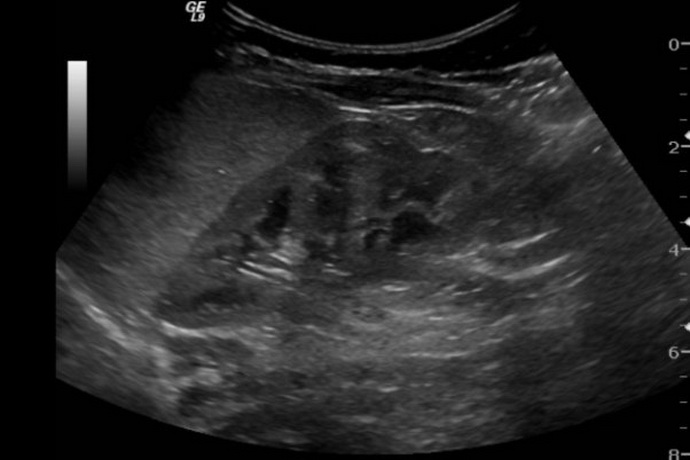

دبیر انجمن رادیولوژی ایران اظهارداشت: سونوگرافی کاری تخصصی است و نقش حیاتی در مدیریت درمان بیماران دارد آموزش آن یک دوره ۴ساله در محیط بیمارستانی و دانشگاهی می‌طلبد و قابل انجام بعد از گذراندن دوره‌های چند روزه و حتی ٢ و٣ ماهه نیست.